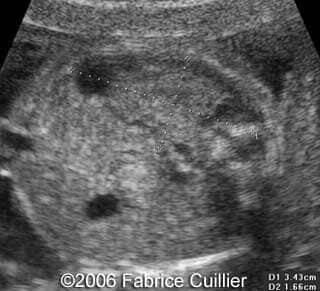

This is a 24- year-old-primigravida scanned at our unit at 21 weeks. During the first trimester, the nuchal translucency and the triple test were normal. At the end of the second trimester, the sonographer diagnosed a left polycystic kidney. The right kidney was normal with a normal corticomedular differentiation. The bladder was also normal. The patient refused additional investigations. We performed a scan at 21 weeks. The ultrasound findings were:

• an abnormal polycystic left kidney (34 X 17 mm) with an abnormal corticomedullar differentiation. This kidney was on the lumbar fossa.

Transverse view of the normal right kidney and the abnormal left kidney